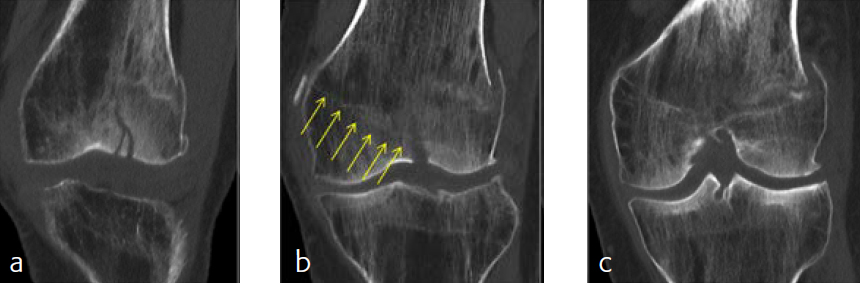

A 79-year-old woman fell downstairs at home and sustained a low-energy distal intraarticular femoral fracture. On conventional x-rays, the fracture seemed to be a unicondylar lateral split-type in rather osteoporotic bone (Fig 1). For detailed fracture analysis, a CT scan was performed that demonstrated a displaced lateral and nondisplaced medial condylar fracture (AO-33C1) (Fig 2). The fracture was very distal and therefore difficult to address with one lateral plate. Using VA technology in this situation provided the advantage of angulating the most distal anterior screw very close to the intercondylar notch in order to address the nondisplaced but fractured anteromedial condyle (Fig 3). Due to poor bone quality, a long plate was used to prevent a future periimplant fracture. Early follow-up showed uneventful healing with good function.